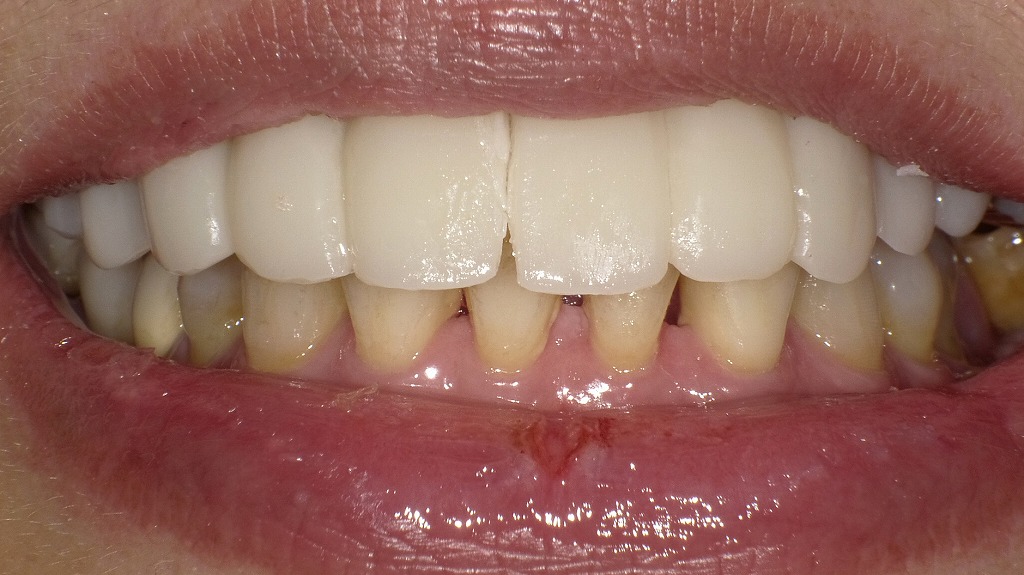

この画像は、右上3番・右上1番・左上5番を支台歯として作製した仮歯(プロビジョナルブリッジ)を装着した状態を示しています。

仮歯(プロビジョナルブリッジ)を装着 🦷 現在の状態

- 支台歯:右上3番、右上1番、左上5番。

- 仮歯の範囲:右上3番から左上5番まで連続した長大ブリッジ型の仮歯が装着されています。

- 形態:前歯部の審美性と発音を考慮した自然なラインで製作されており、咬合高径・唇側形態も良好です。

💡 仮歯の目的

- 審美性の回復:術後の外観を一時的に整え、日常生活での違和感を軽減。

- 咬合・発音の確認:咬合関係や発音バランスを調整し、最終補綴物の参考に。

- 歯肉形成誘導:特に前歯部では仮歯の形態により、歯肉ラインの自然なカーブを整える効果がある。

🔍 今後の予定

- 骨造成とインプラント埋入部(右上2番、左上1〜4番)の治癒経過を観察しながら、最終補綴設計へ進行。

- インプラントのオッセオインテグレーション完了後、仮歯のデザイン・咬合を参考に最終ブリッジまたは連結冠を製作予定。